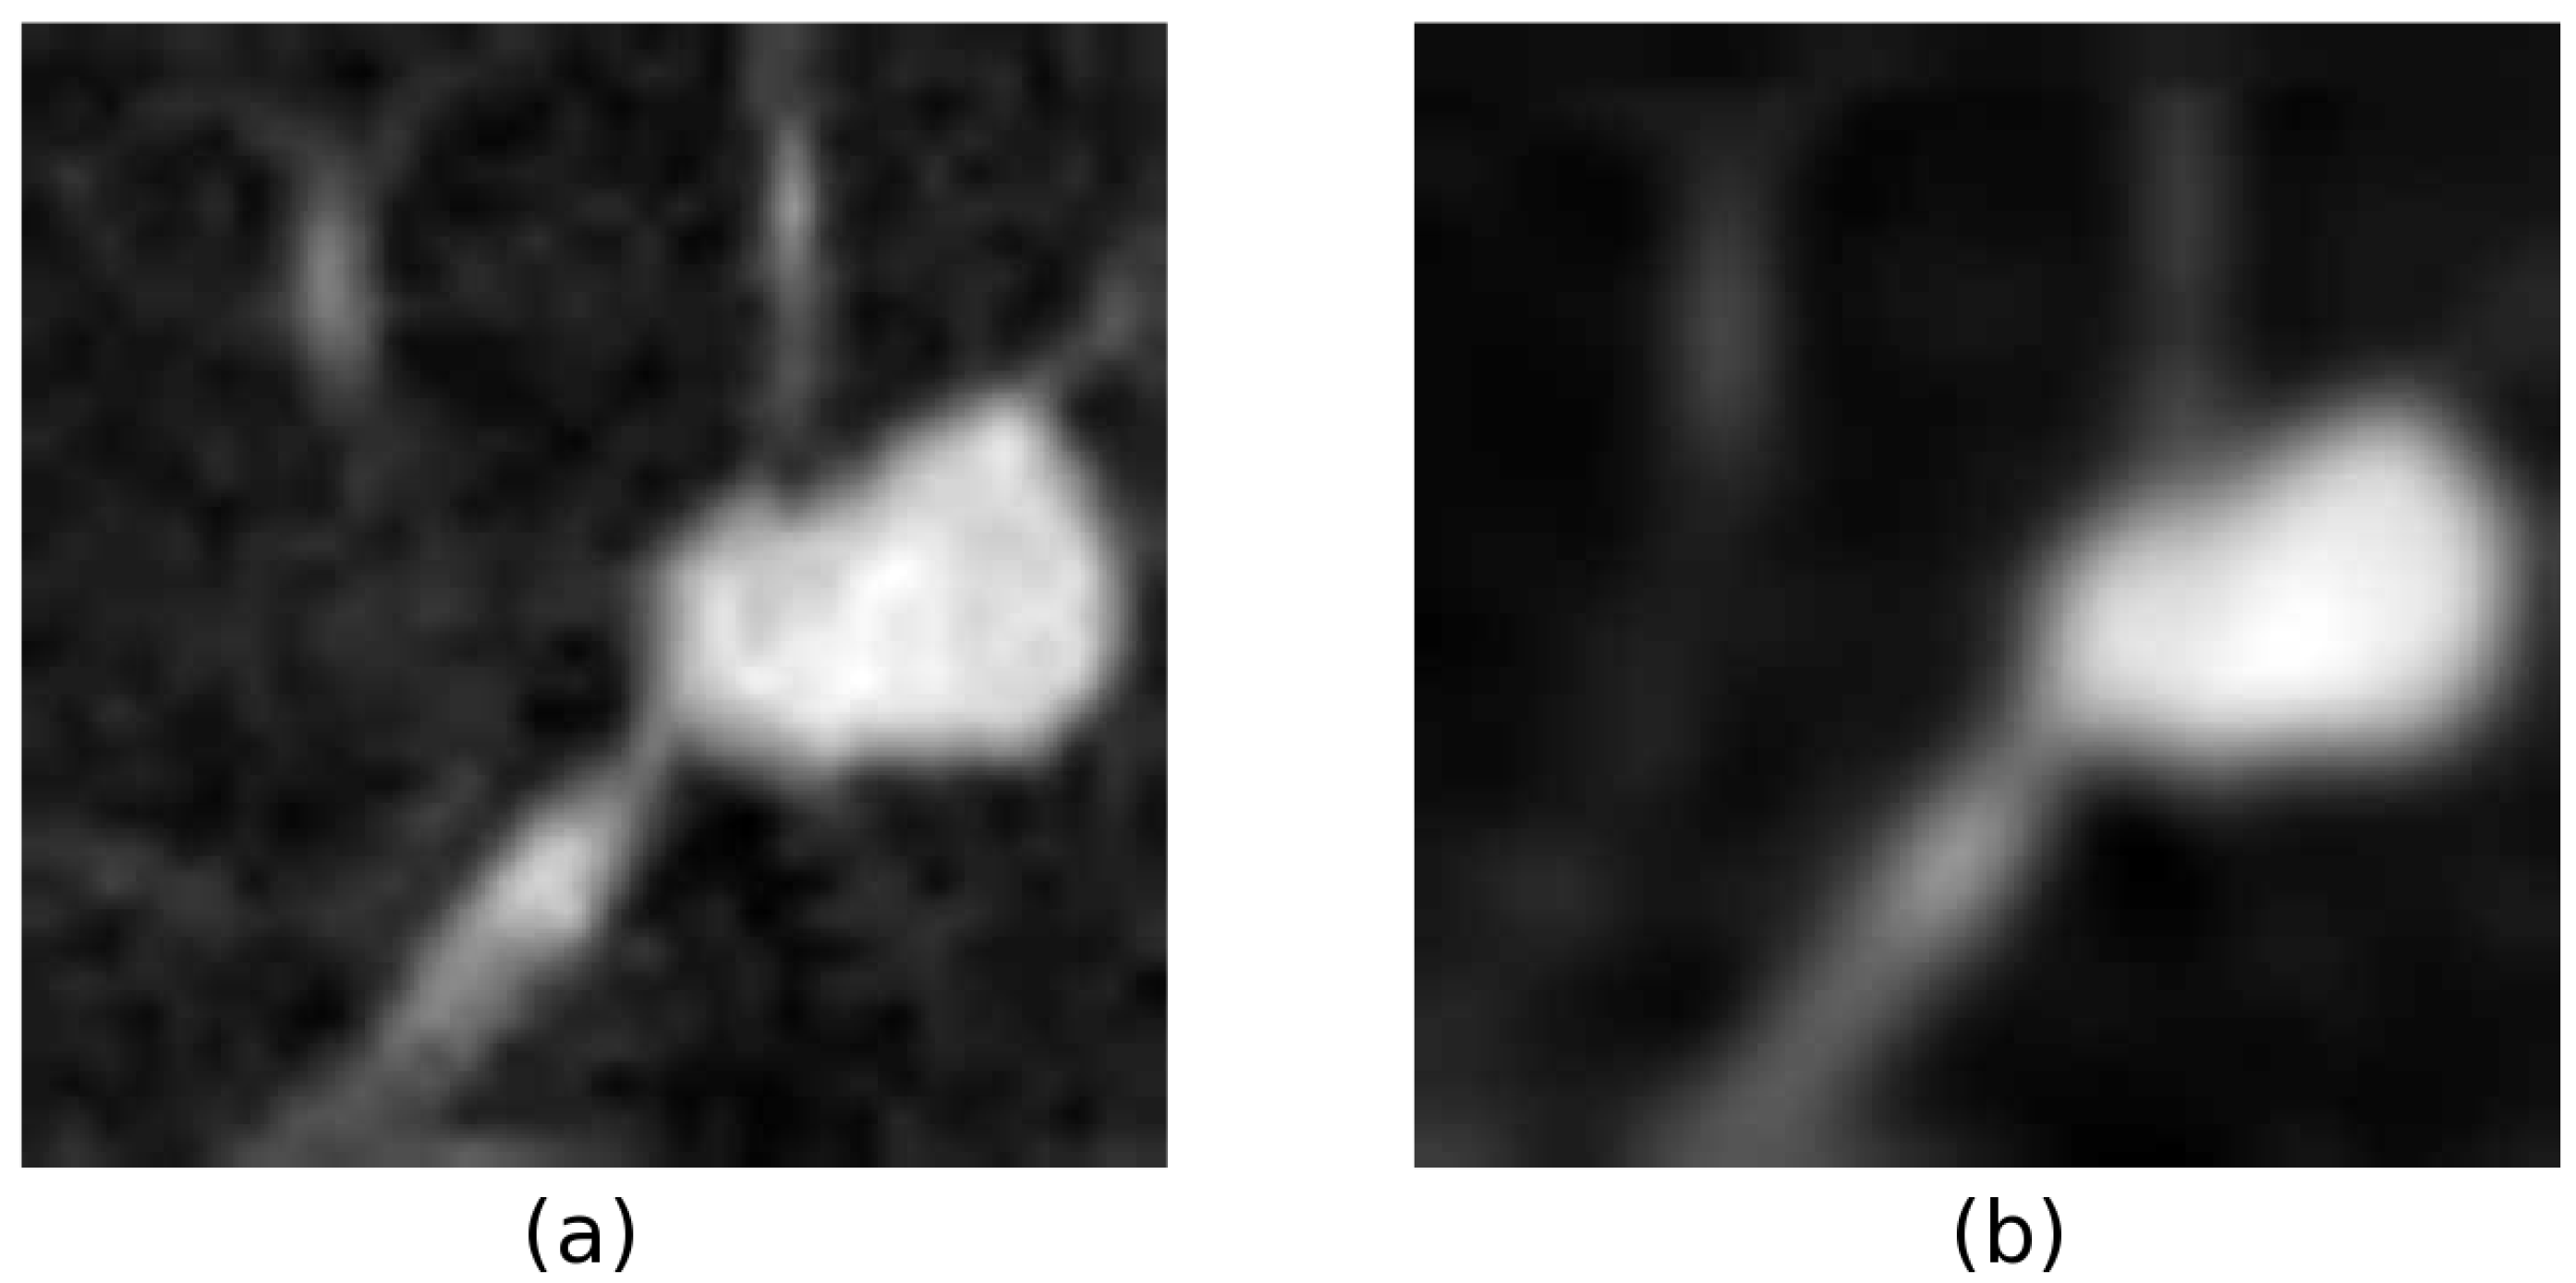

4. Nodule Candidates Selection Based on Block Analysis

4.1. Block Image Enhancement

4.2. Block Segmentation and Location Adjustment